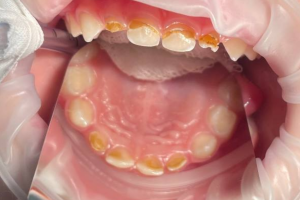

Семейная областная стоматология "Кидди Дентал" - это команда компетентных врачей, каждый из которых знает и любит свое дело. Опыт наших врачей, использование современного оборудования и надежных материалов позволят проводить лечение любой сложности.